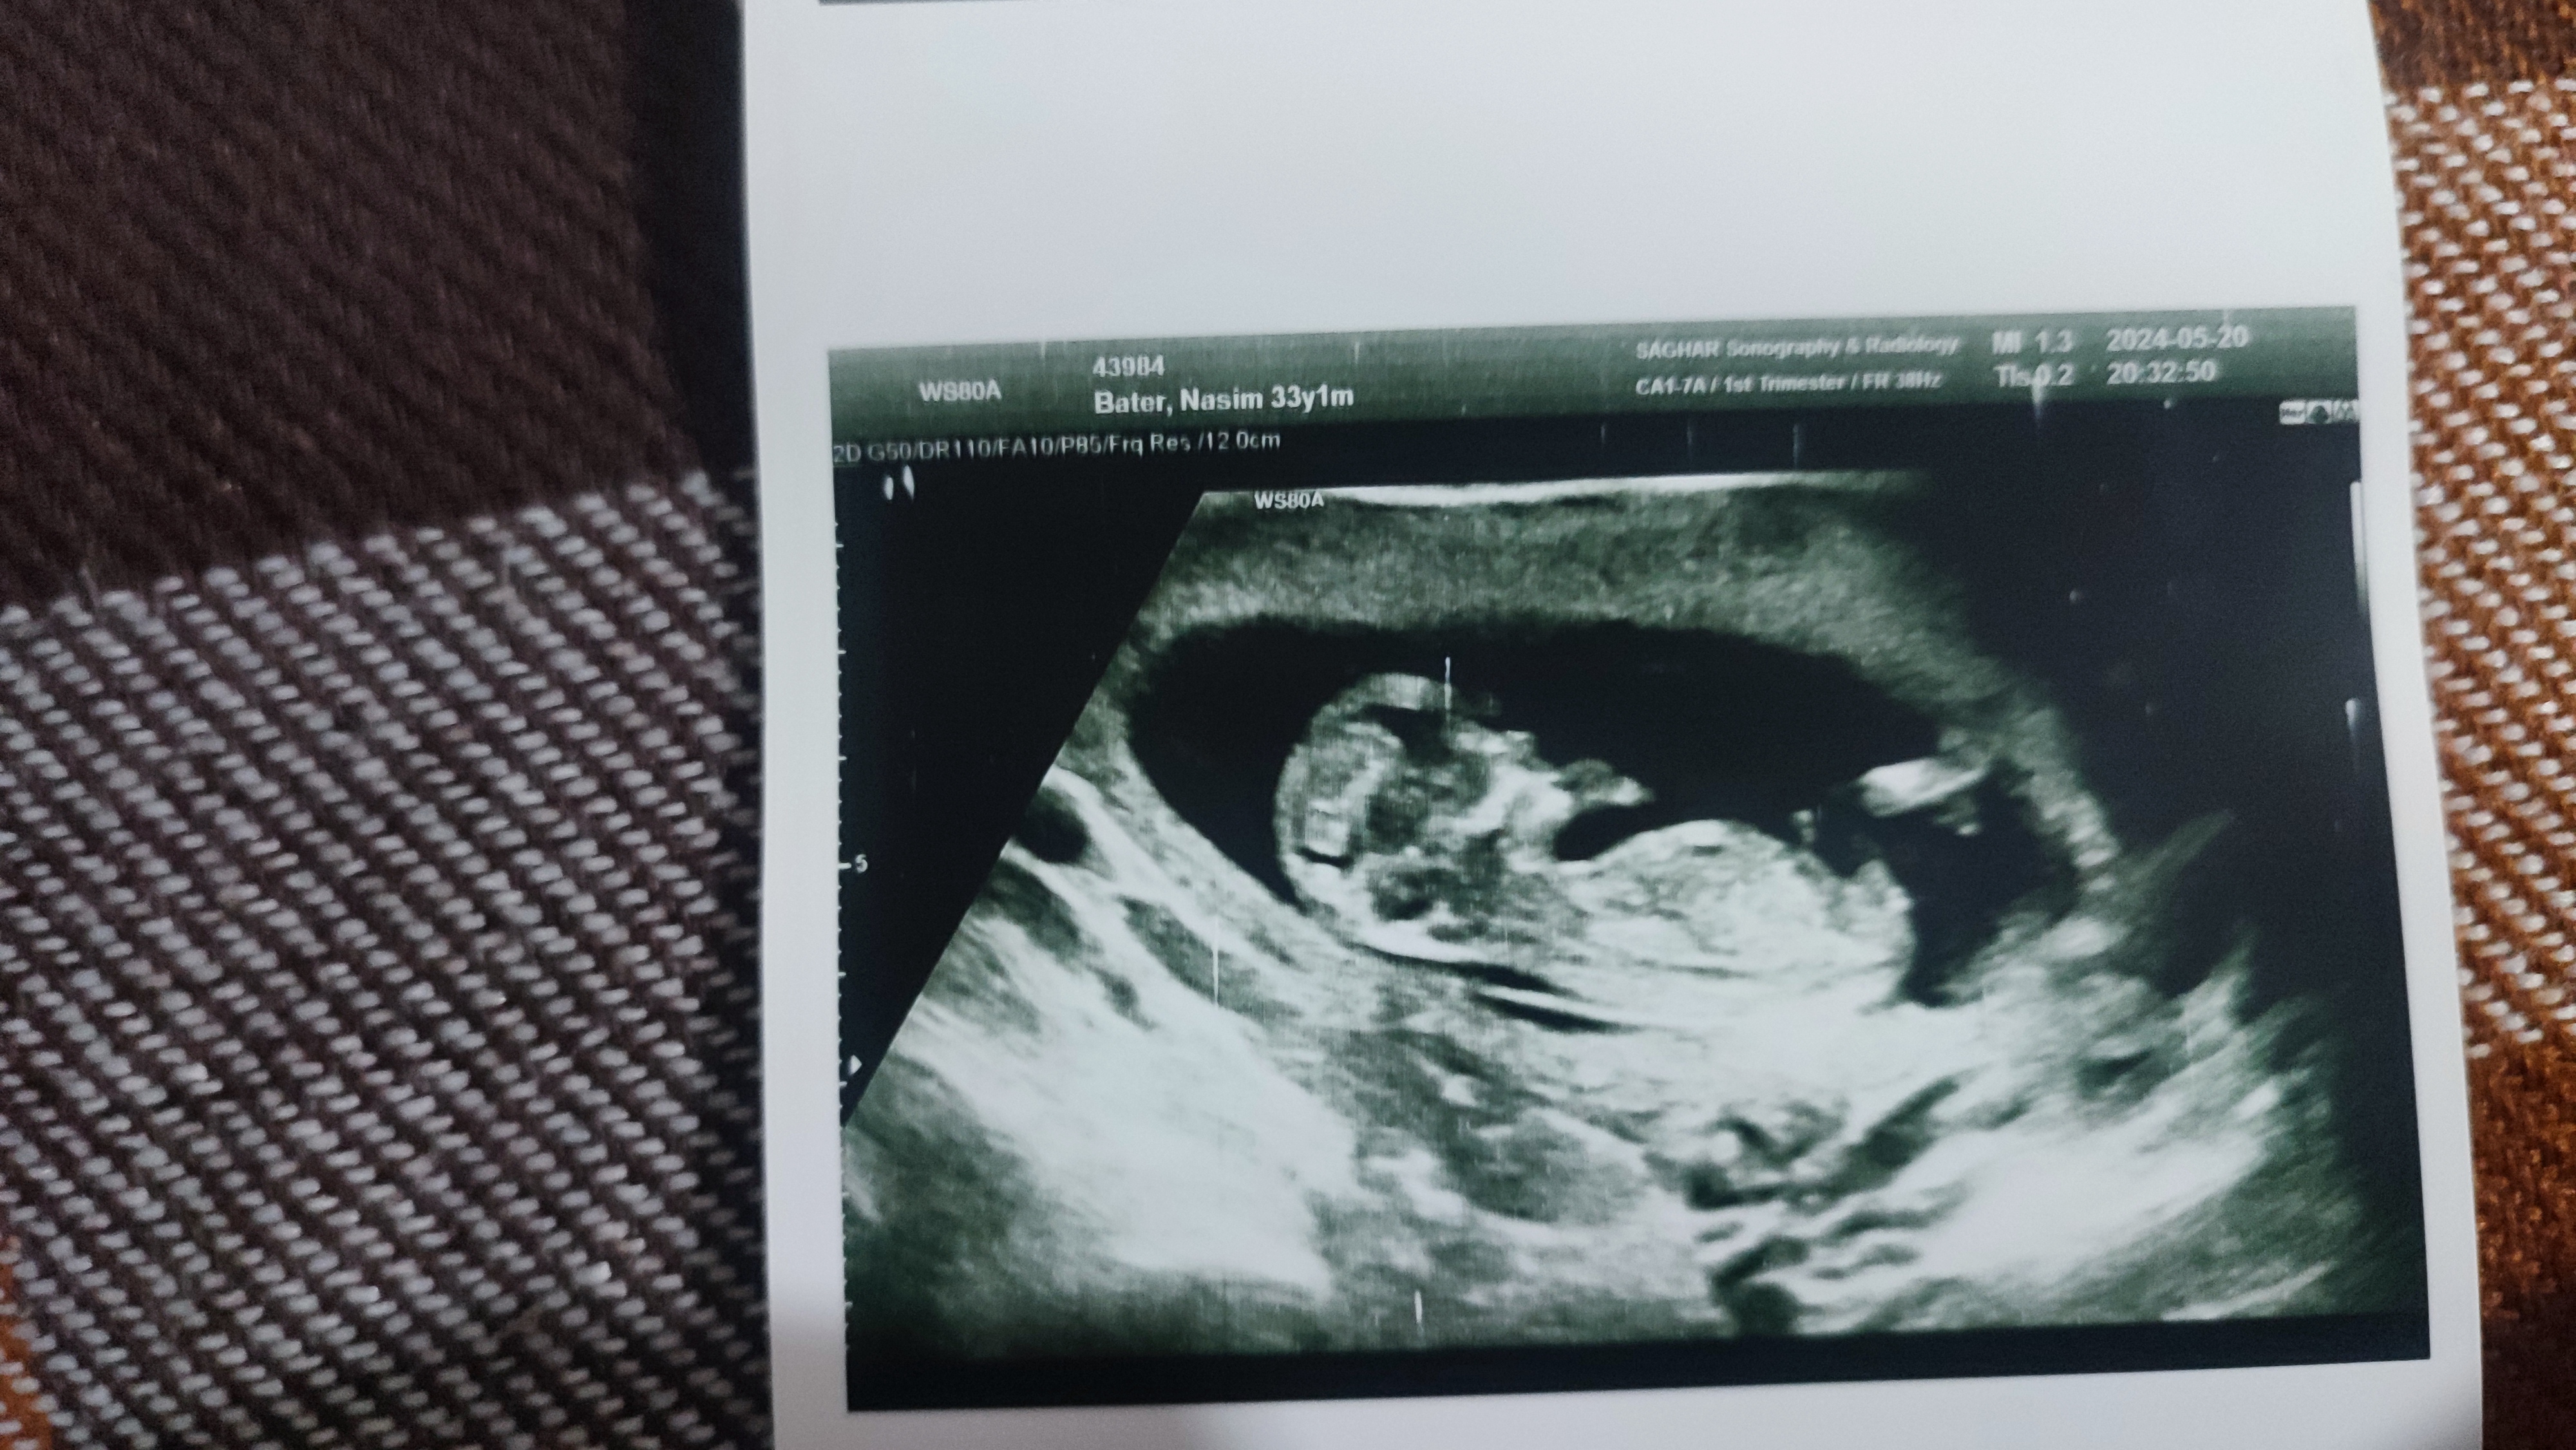

_zan_shisheii_ مدیر استارتر عضویت: 1398/08/11 تعداد پست: 797 عنوان سونو ان تی عکس و جنسیت 167 بازدید | 21 پست سلام .دوستان میتونید جنسیت جنین هارو تشخیص بدید؟ تبریک 1 5 10 15 20 25 30 35 40 1404/05/20 | 00:34 0 نفر لایک کرده اند ... گزارش تاپیک نامناسب

_zan_shisheii_ مدیر استارتر عضویت: 1398/08/11 تعداد پست: 797 هرکس میتونه حدس بزنه ،بچه ها سه تا هستن یکیش مال کنه بقیه ما بچه پسرخالمه تبریک 1 5 10 15 20 25 30 35 40